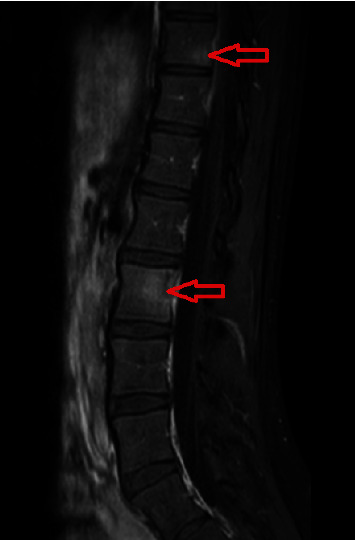

Cat scratch disease (CSD) typically presents as a self-limiting lymphadenopathy associated with a cat bite or scratch and commonly affects children and young adults. Atypical manifestations, involving the eyes, nervous system, heart, liver, spleen, skin, and musculoskeletal system, could be severe and difficult to diagnose, and they could occur in 5%-20% of the cases. Herein, we report an unusual case of CSD with multifocal osteomyelitis. A 15-year-old girl presented with right axillary lymphadenopathy. Since she had a history of cat scratch, azithromycin was started for CSD. Two days later, she was readmitted to our hospital with severe back pain which required differential diagnosis. Lumbar spinal magnetic resonance imaging (MRI) revealed multifocal vertebral osteomyelitis. The patient was hospitalized, and then teicoplanin and cefotaxime were added to the azithromycin therapy. After excluding the possible other causes, the definitive diagnosis of osteomyelitis secondary to CSD was made upon the combination of the MRI scan findings of the vertebrae, histopathological investigation of excisional right axillary biopsy, positron-emission tomography/computed tomography (PET/CT), and Bartonella henselae serologies. Atypical manifestations of CSD are widely variable; therefore, it should be kept in mind in the differential diagnosis of severe musculoskeletal pain and osteomyelitis.

猫抓病(CSD)通常表现为与猫咬伤或抓伤相关的自限性淋巴结病,常见于儿童和青壮年。非典型表现可累及眼睛、神经系统、心脏、肝脏、脾脏、皮肤和肌肉骨骼系统,病情严重且难以诊断,约占病例总数的5%-20%。在此,我们报告了一例不同寻常的 CSD 合并多灶性骨髓炎病例。一名 15 岁女孩因右腋窝淋巴结肿大就诊。由于她有猫抓病病史,医生开始使用阿奇霉素治疗 CSD。两天后,她因剧烈背痛再次入院,需要进行鉴别诊断。腰椎磁共振成像(MRI)显示她患有多灶性脊椎骨髓炎。患者住院后,在阿奇霉素治疗的基础上加用替考拉宁和头孢他啶。在排除了其他可能的病因后,结合椎体的核磁共振扫描结果、右腋窝切除活检的组织病理学检查、正电子发射断层扫描/计算机断层扫描(PET/CT)和鸡巴氏杆菌血清学检查,最终确诊为继发于 CSD 的骨髓炎。CSD 的非典型表现千变万化;因此,在鉴别诊断严重肌肉骨骼疼痛和骨髓炎时应牢记这一点。